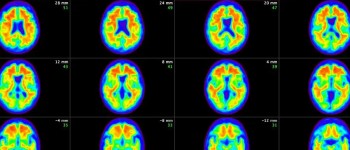

Під час дослідження вчені зосередилися на тому, як білок тау порушує хімічний зв'язок між нейронами.

При хворобі Альцгеймера тау білок накопичується в мозку та перешкоджає нормальним процесам у синапсах, використовуючи тип ферменту, званого динаміном, ключового компонента синаптичної функції здорових нейронів.

Мабуть, ін'єкція пептиду запобігає цій взаємодії з динаміном, що потім призводить до зворотного розвитку симптомів хвороби Альцгеймера у мишей та відновлення їх когнітивних функцій, якщо їх почати лікувати на ранній стадії.